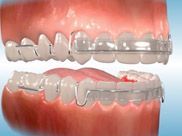

Other types of orthodontic appliances may also be used during the course of treatment. Some of these appliances are removable and can be taken in and out of the mouth, while others will be attached to the teeth until they are no longer needed.

Depending upon the specific needs of the case, these appliances may be used to accomplish a number of things including:

- Widening the jaws to make sufficient space for permanent teeth

- Influencing jaw growth

- The reduction of deep overbites

- Allowing the correction of teeth in crossbite

- Maintaining the space for a permanent tooth when a baby tooth has been prematurely lost

- Minor tooth movement

- Helping to control harmful oral habits